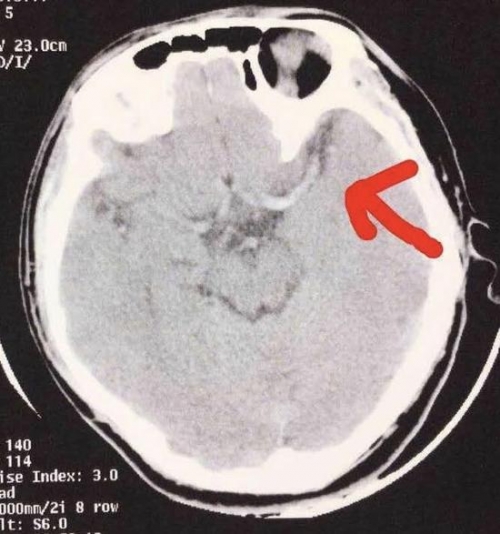

Tiểu Tạ bị tắc nghẽn động mạch não ở phần giữa.

Khi chuyển tới bệnh viện ở Hồ Nam, da của Tiểu Tạ đã xanh xao, nhợt nhạt hơn trước rất nhiều. Cậu được chẩn đoán tắc nghẽn động mạch. Phương pháp điều trị nhanh chóng và hiệu quả nhất là phẫu thuật loại bỏ các huyết khối tắc nghẽn.